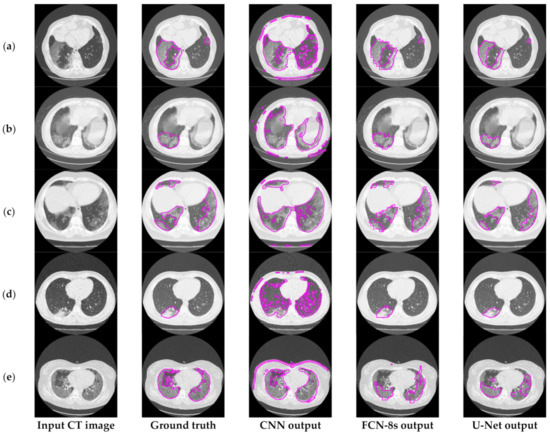

6.3.2. The Performance of the Proposed Few-Shot U-Net Model